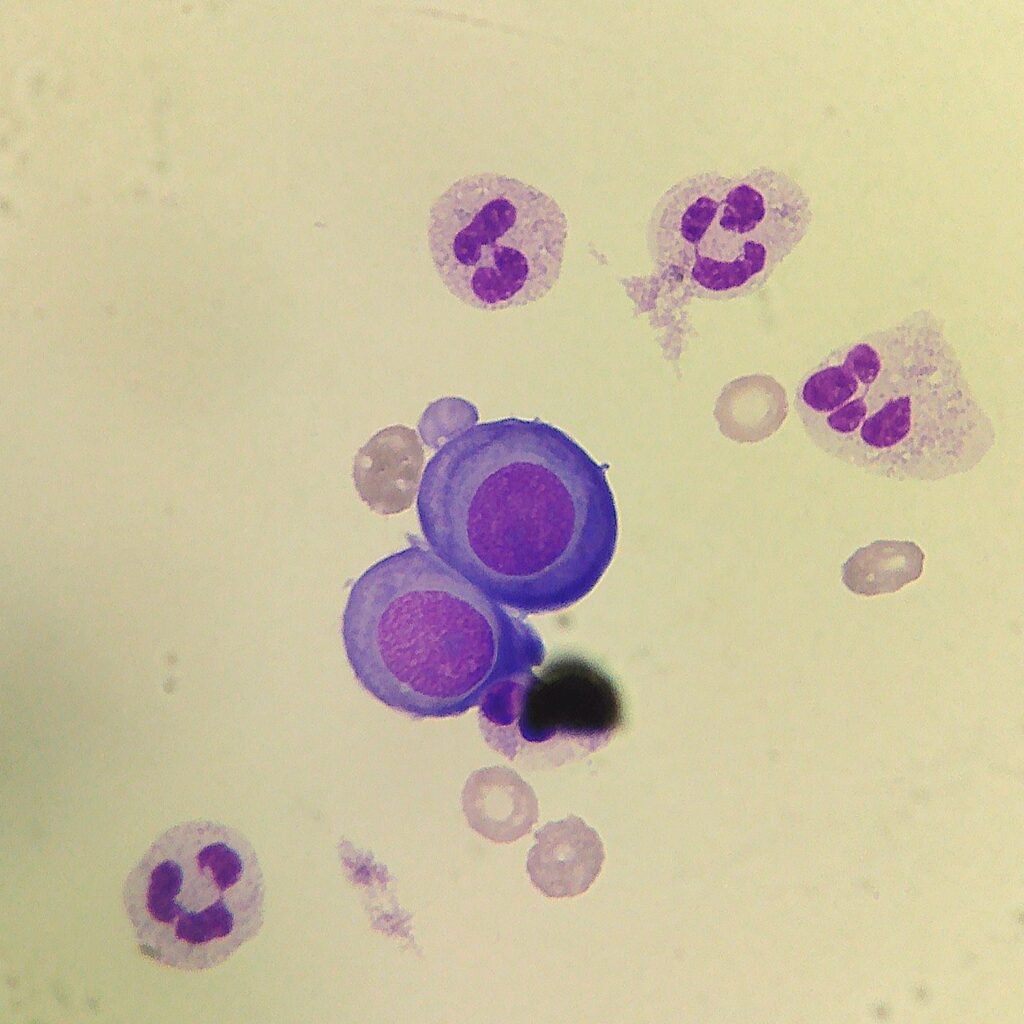

Mesothelial cells are described as having a “fried egg” appearance. They have a round to oval nucleus with smooth borders and evenly distributed chromatin. Nucleloli are usually present. Mesothelial cells may also be multinucleated.

Macrophages are about the same size as mesothelial cells, so the two can often be confused. Macrophages can usually be differentiated by the presence of vacuoles and a lacey chromatin. If both cell types are present and differentiation is difficult, take a look around the slide to get an idea of each kind of morphology before starting a differential.